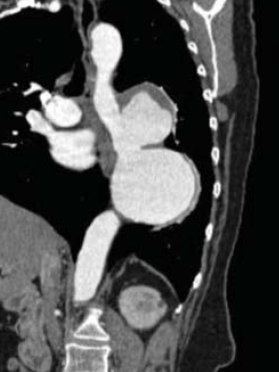

2. ábra.

PAU az aorta ascendensen.